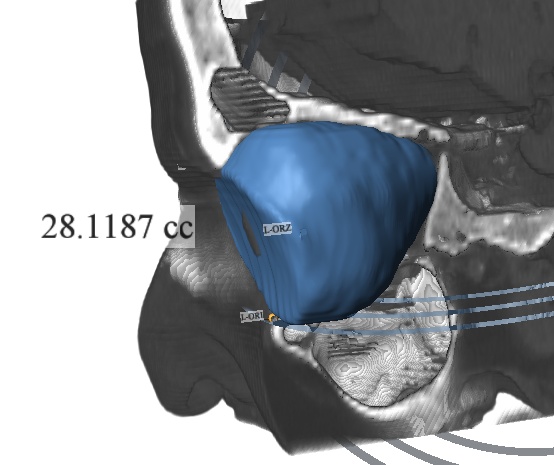

Stratovan Maxillo™ computes orbit (eye socket) volumes and bony contour shapes directly from x-ray computed tomography (CT) image data. Maxillo is intended for research use only by otolaryngologists, ENTs, plastic, and maxillofacial researchers investigating orbit morphology, shape, volume, and globe position. Maxillo utilizes a patent-pending image segmentation method.